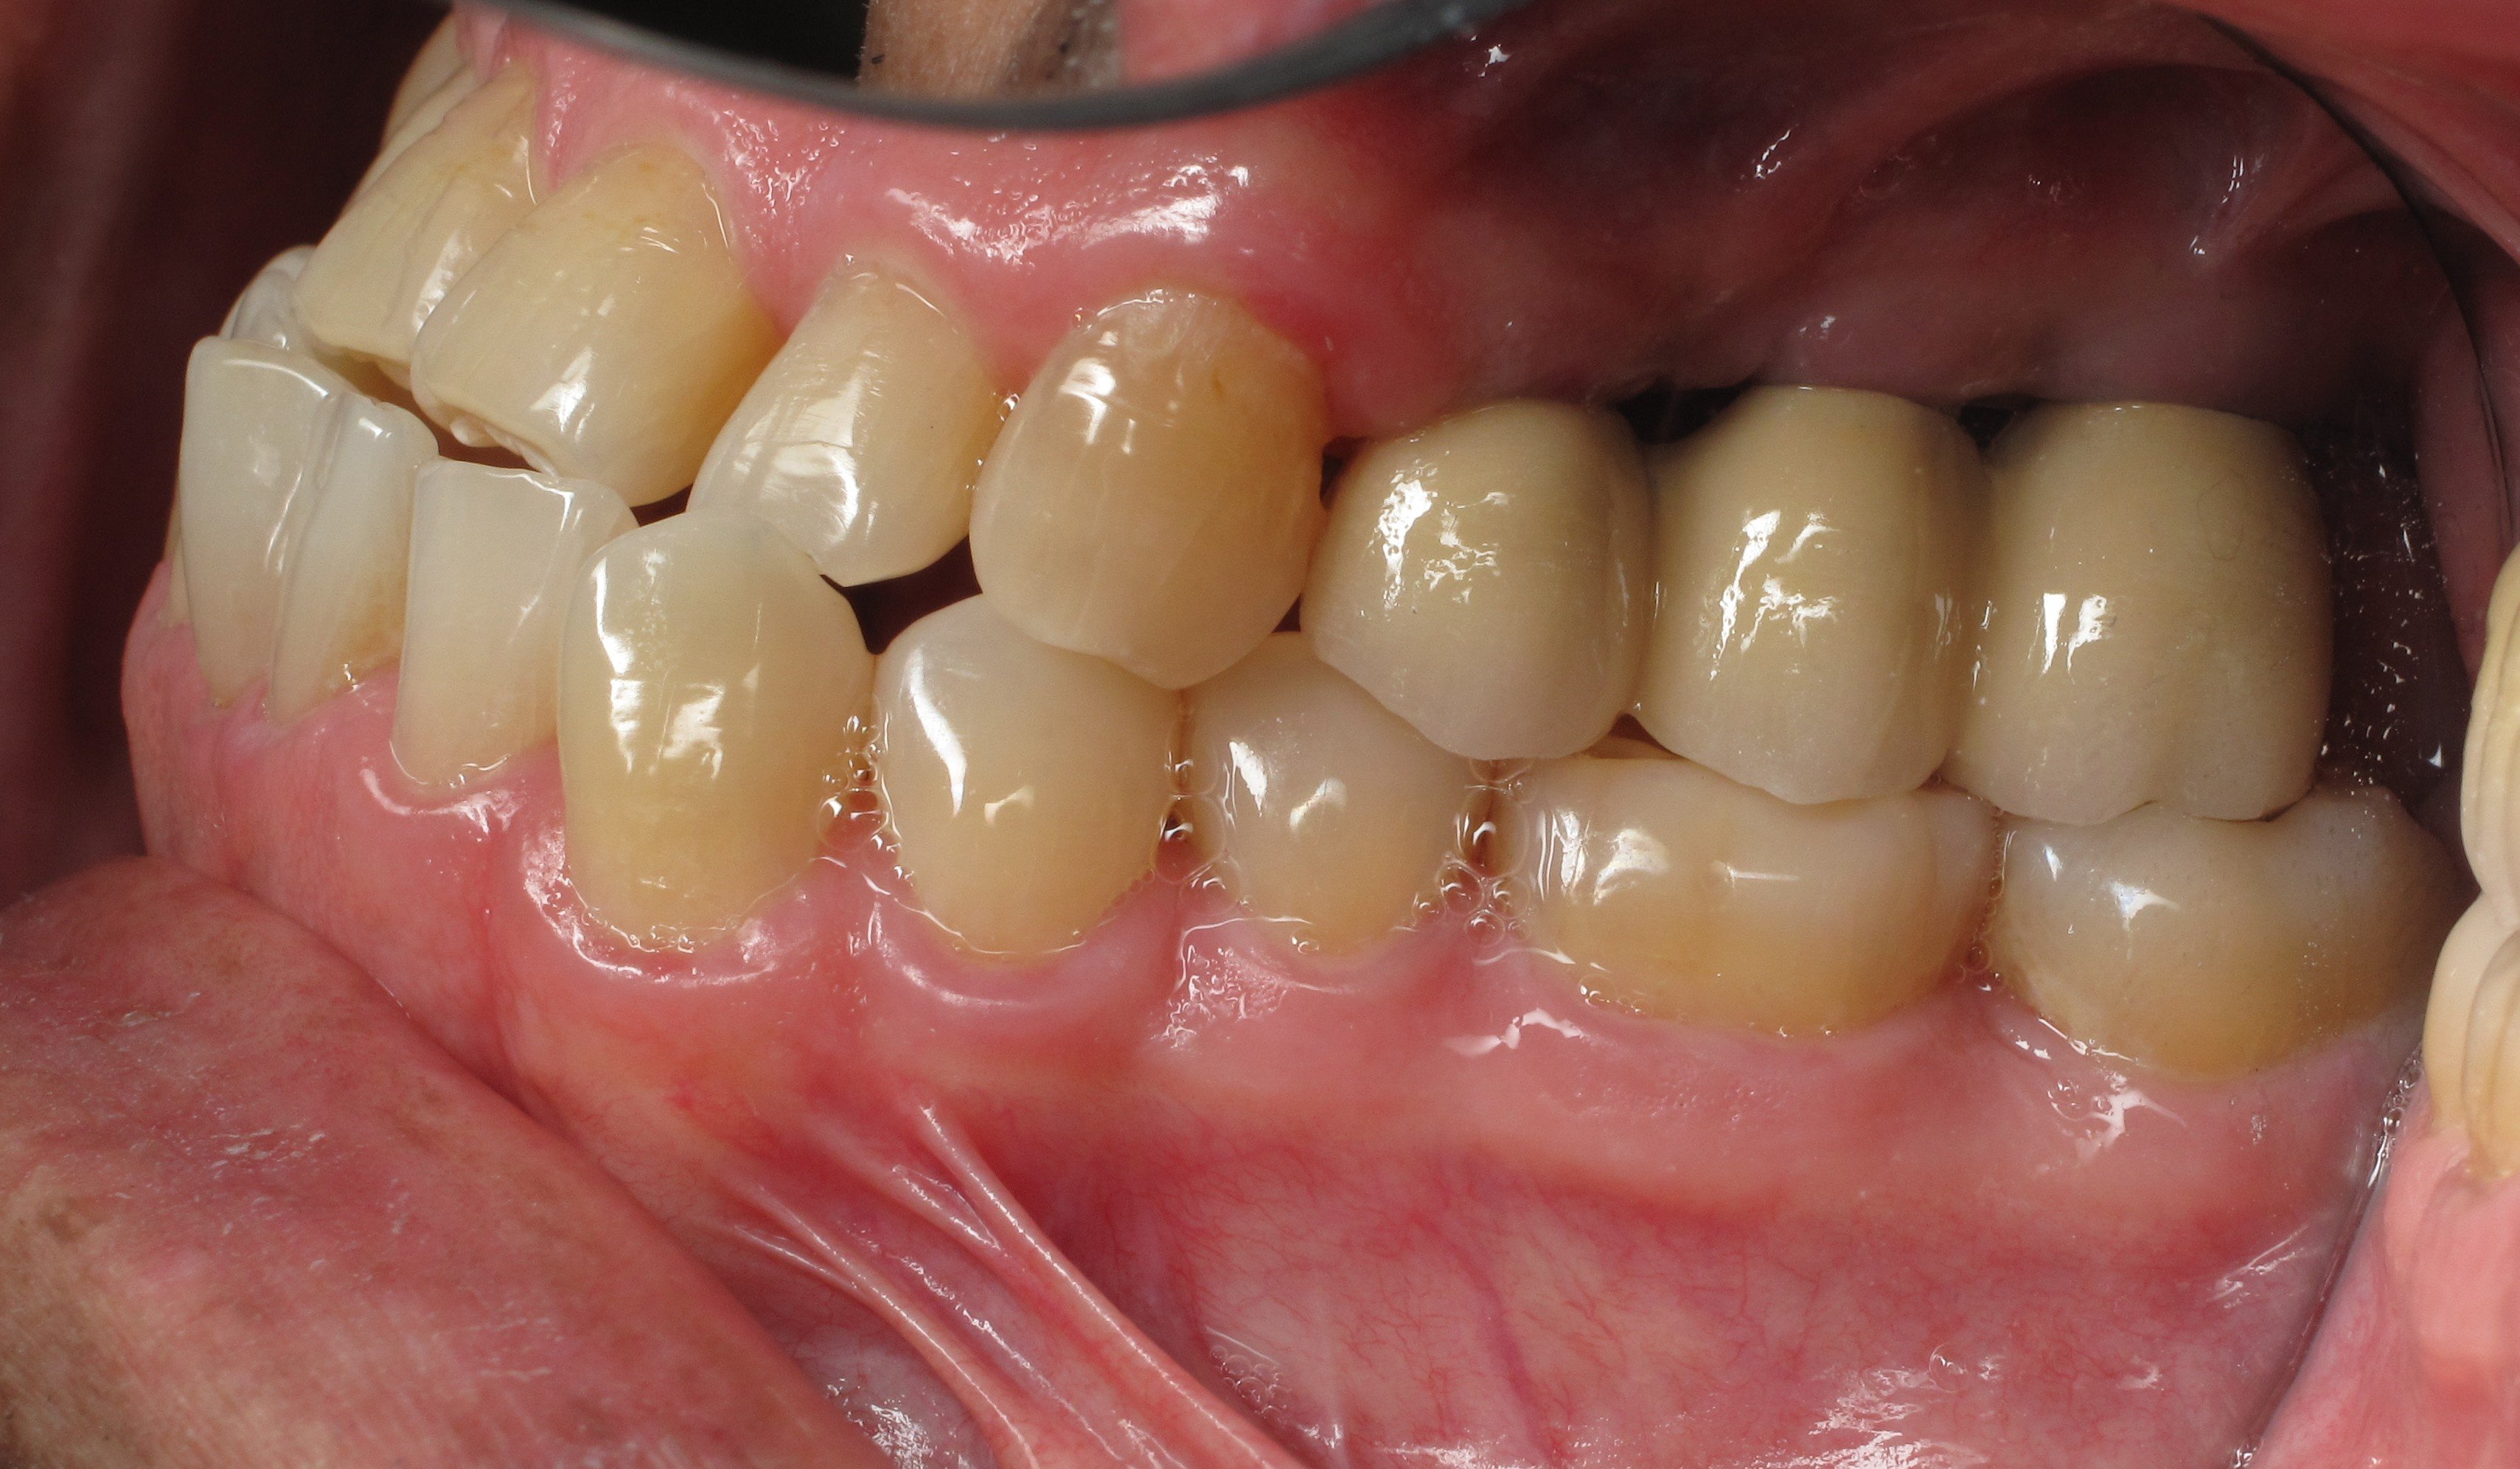

Replacing missing molar tooth with dental implant and zirconia crown Dental Implant Molar Tooth Cost Having difficulty chewing because of a missing tooth? Dental implants are a time tested solution to restoring missing teeth. What factors affect the cost of dental implants? On average, the cost for a single dental implant in singapore ranges from sgd 3,000 to sgd 6,000. Here are some of the costs. What is the cost of dental implants in singapore?. Dental Implant Molar Tooth Cost.